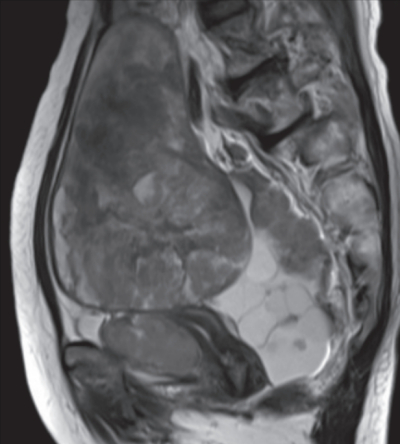

血液所見:赤血球 370 万、Hb 10.8 g/dL、Ht 32 %、白血球 8,800、血小板 19 万。血液生化学所見: 総蛋白 6.8 g/dL、アルブミン3.3 g/dL、総ビリルビン 0.9 mg/dL、AST 28 U/L、ALT 40 U/L、尿素窒素 20 mg/dL、クレアチニン 0.8 mg/dL、CEA 2.8 ng/mL(基準 5 以下)、CA19-9 30 U/mL(基準 37 以下)、CA125 1,280 U/mL(基準 35 以下)。CRP 1.0 mg/dL。骨盤部 MRI T2 強調水平断像、矢状断像及び腹部造影 CTを別に示す。審査腹腔鏡(腹腔鏡下試験切除術)で、腫瘍の播種病変との癒着により骨盤内臓器の同定はできず、腫瘍生検のみ施行した。病理診断の結果は高異型度漿液性癌であった。